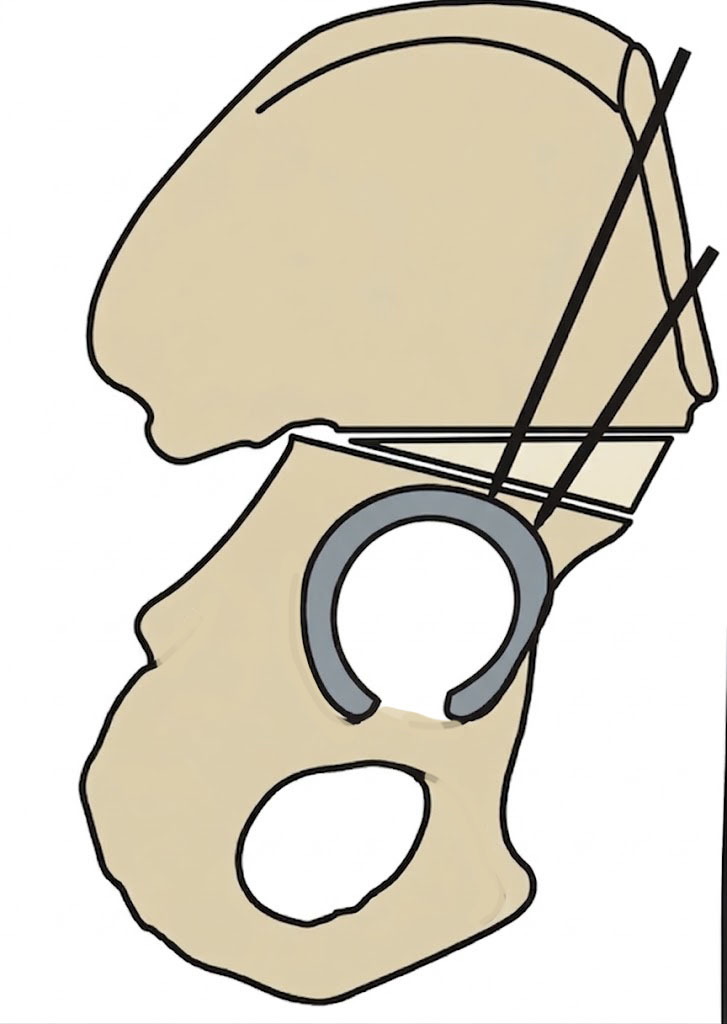

Salter osteotomy |

Salter Redirectional Osteotomy

Indication

Anterolateral acetabular deficiency with concentric acetabular shape

Younger patient < 8 years - osteotomy rotates through flexible pubic symphysis

Technique

Osteotomy

- through greater sciatic notch to between ASIS and AIIS

- Gigli saw passed around greater sciatic notch

- osteotomy posterior to anterior

- acetabulum rotated anteriorly and laterally

- 15 mm triangular graft from iliac crest apophysis

- secure with K wire fixation

Salter complete osteotomy